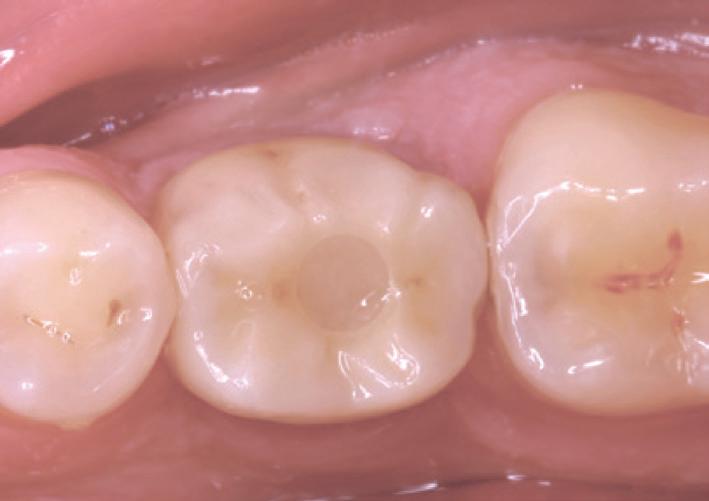

Additionally, new AI-assisted software accelerates the entire implant planning process by automating time-consuming tasks. Now, preparing data for implant cases— like merging CBCT volumes with digital impressions—designing virtual crowns and digitally placing implants is all handled automatically, making implant planning faster and easier. When combined with a prosthetic-driven approach, these software updates improve treatment predictability and give doctors the confidence to deliver precise and successful implant outcomes.